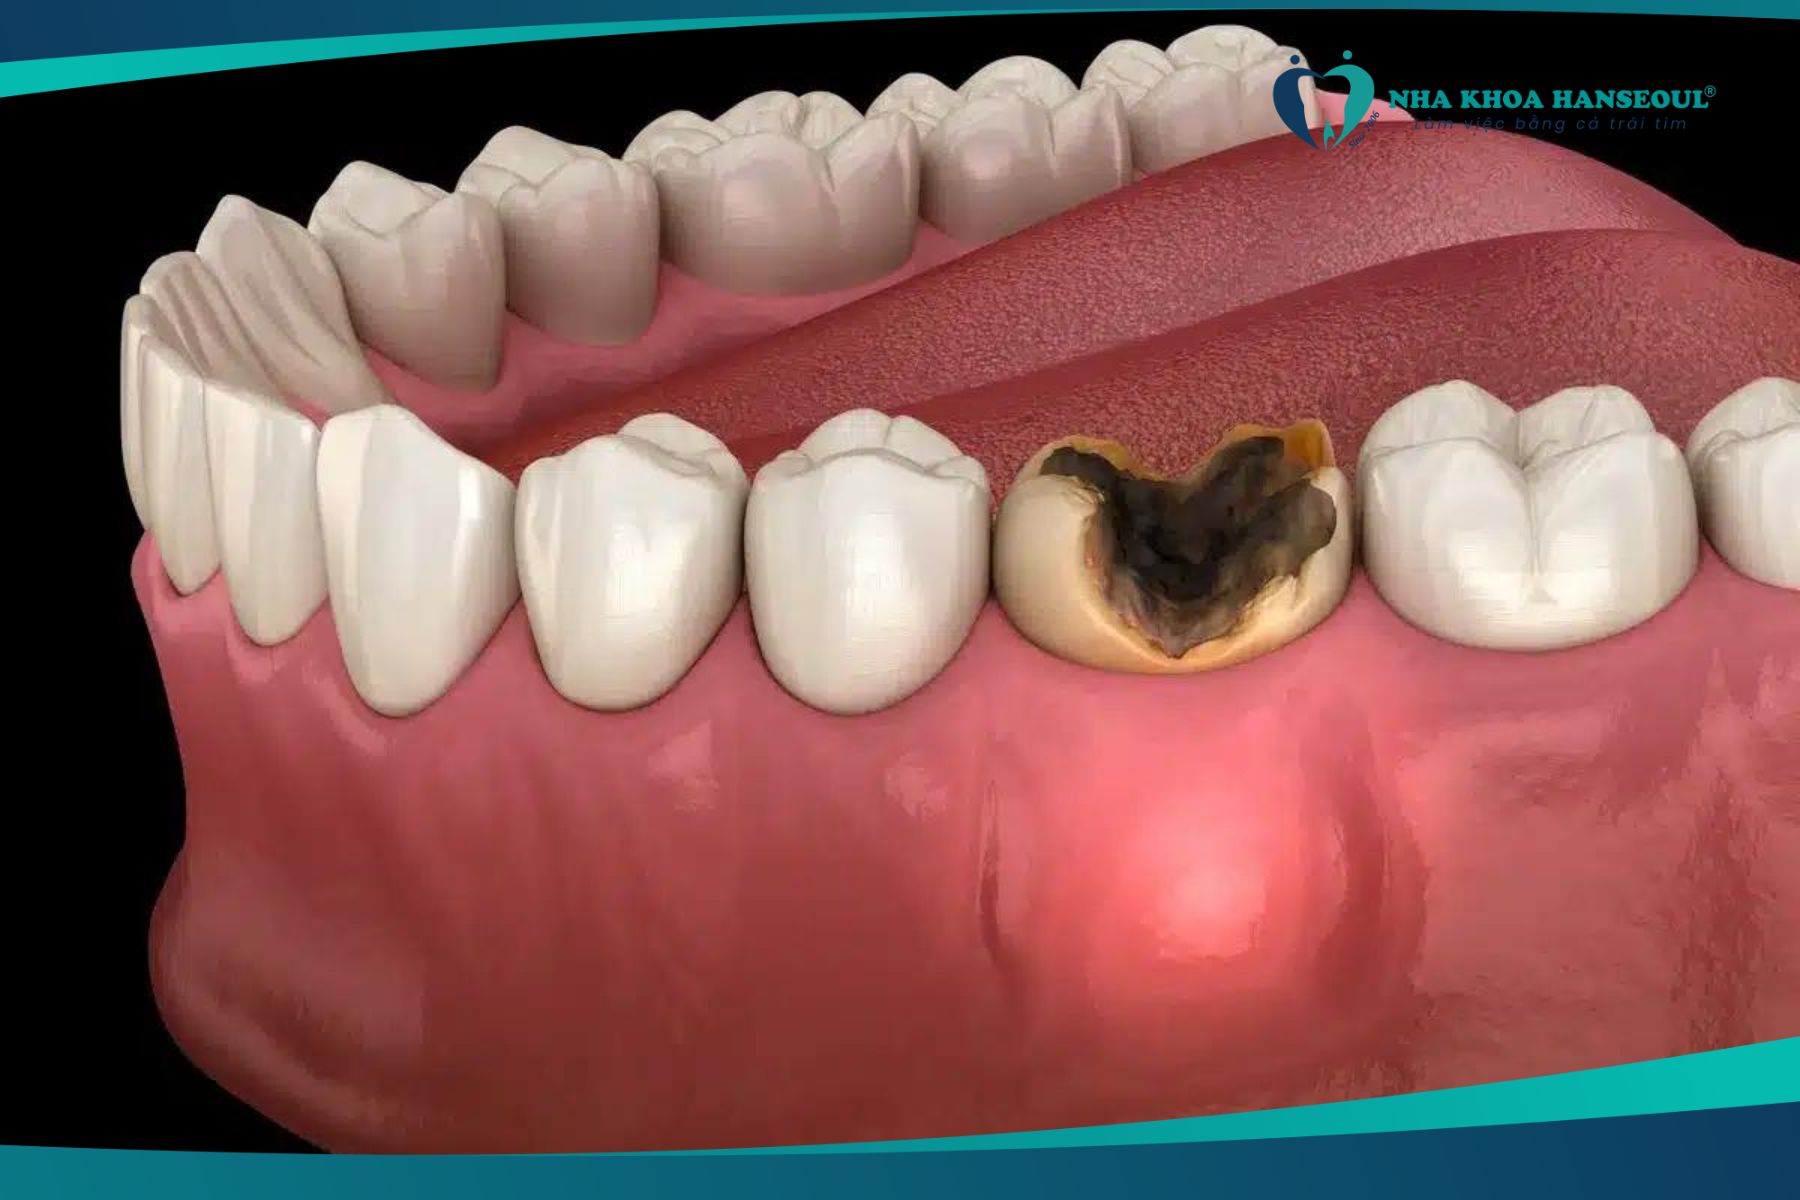

Răng sâu nặng gây mất thẩm mỹ

Khi bị sâu răng nặng sẽ ảnh hưởng đến thẩm mỹ của bề mặt răng một cách nghiêm trọng. Dấu hiệu phổ biến khi tình trạng răng sâu đã ở mức độ nặng hơn chính là toàn bộ phần men răng bị phá hủy, lộ ra phần tủy răng bên trong làm cho cho răng bị sâu đen. Do đó, khi giao tiếp sẽ khiến người đang bị sâu răng nặng cảm thấy tự ti và mặc cảm.

Sâu răng gây mất thẩm mỹ